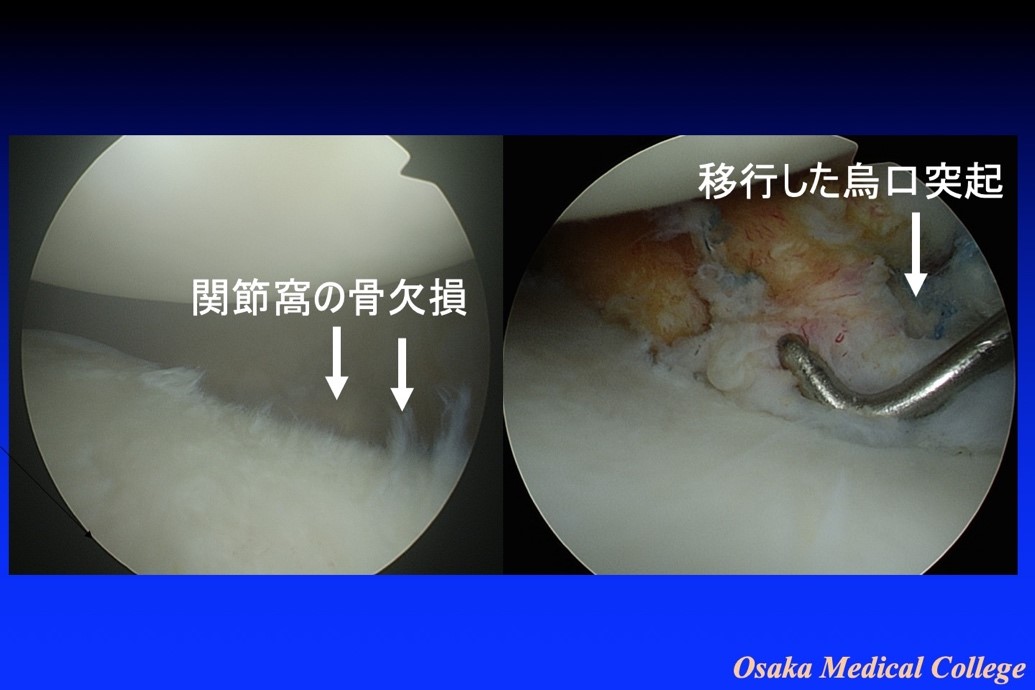

Amazon.co.jp: 肩関節鏡視下手術 (ビジュアル・サージカル。鏡視下バンカート修復術|森大祐(京都)。関節鏡・スポーツ整形外科センターのご紹介 | 診療科・診療。ベトナムチョコ LAVA 30枚入り。肩 脱臼 手術 | あんしん病院。関節鏡視下手術 ~肩、膝、スポーツ障害へのアプローチ~。腱板断裂に対する低侵襲手術 −関節鏡視下腱板修復を中心に。肩・肘の外科 - 大阪医科薬科大学整形外科学教室。肩関節センター | 整形外科 | 倉敷中央病院。関節鏡・スポーツ整形外科センターのご紹介 | 診療科・診療。主な肩関節鏡手術 | 肩関節鏡手術の職人 鈴木隆。関節鏡視下手術 | AR-Ex 尾山台整形外科。鏡視下肩関節唇形成術後にソフトテニスに復帰された患者様 | AR。「肩関節鏡視下手術」石橋 恭之 / 三幡 輝久定価: ¥ 16000 マーカー、書き込みありません裁断済みです